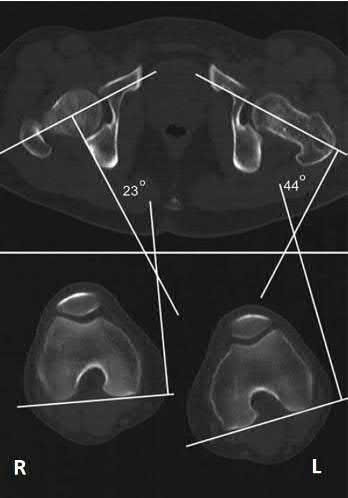

A 26-year-old male underwent statically locked intramedullary nail fixation for a comminuted left femur fracture. An early post-

operative computed tomography (CT) scanogram was taken to check rotational alignment, as shown in Figure A. What would be the next best step in the management of this patient?

The CT scanogram shows the operative left femur is 8 degrees externally rotated compared to the native right femur. No correction is required unless malalignment is >15 degrees and symptomatic. Therefore, the most appropriate next step would be to continue with postoperative observation and close follow-up.

The primary purpose of CT scanogram is to measure the angle of rotation of the femoral neck relative to the femoral condyle. To do this, the right and left femurs must be scanned together using a 5mm helical slice scanner at the hip and knee. The first slice should reveal the alignment of the femoral neck, so as to allow for measurement of the femoral neck-to-horizontal (FNH) angle. The second slice should reveal the alignment of the posterior femoral condyles.

This allows measurement of the posterior condyle-to-horizontal (PCH) angle. Finally, to calculate the rotational alignment (RA), the FNH angle and PCH angles are subtracted (e.g., RA = FNH - PCH). Normal RA is usually +5 to +20 degrees, which is also referred to as 5 to 20 degrees of femoral anteversion.

Lindsey et al. reviewed femoral malrotation following intramedullary nail fixation. They showed the incidence of rotational malalignment was ~28%. Normal femoral neck anteversion (angle of the femoral neck relative to the transverse axis through the femoral condyles) is ~11-13°. However, they noted that some patients have up to 15° difference in rotation in native limbs.

Therefore 15 degrees and symptomatic.